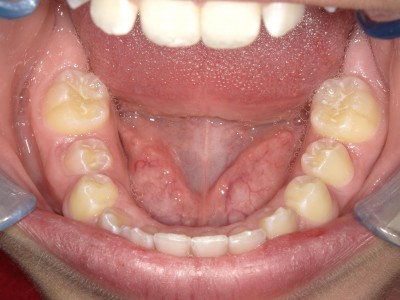

Retentie: Wrap + C-C bar onderkaak